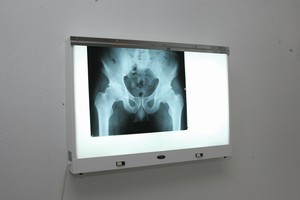

Pažangiausios radiologijos technologijos šiandien leidžia greitai diagnozuoti pacientų būklę bei paskirti jiems patį tinkamiausią gydymą.

Radiologija ypač reikšminga vykdant ankstyvąją vėžio diagnostiką, vertinant įvairias traumas ir ligas, atliekant invazines operacijas.

Specialistai pastebi, kad dauguma žmonių mano, jog radiologija apsiriboja vien tik rentgenografija. Tačiau ši medicinos sritis gerokai įvairesnė.

Šiuo metu gydymo įstaigose naudojama rentgeno, kompiuterinės tomografijos, magnetinio rezonanso tomografijos, angiografijos, branduolinės diagnostikos, spindulinės terapijos bei ultragarso medicininė įranga.